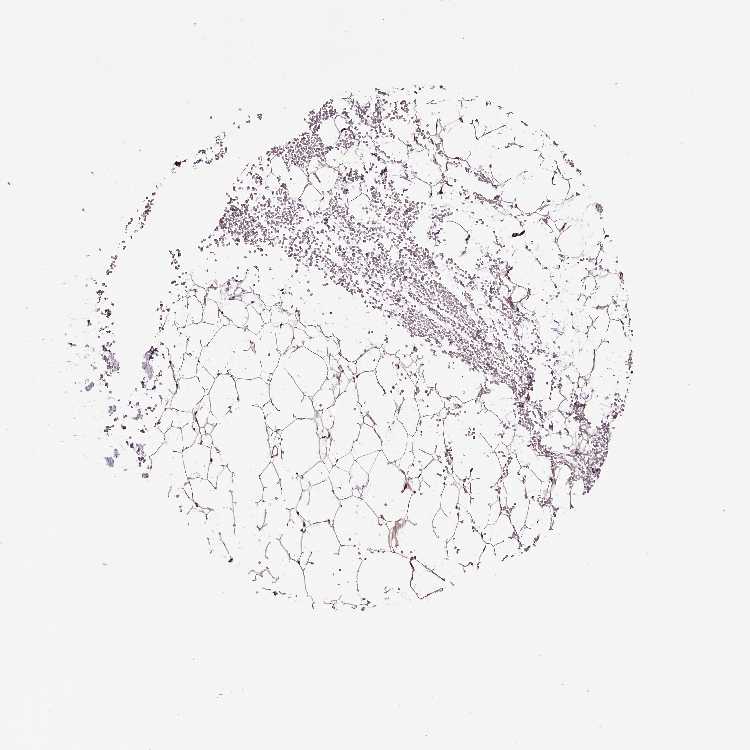

TISSUE PRIMARY DATA SOFT TISSUE Show tissue menu

SOFT TISSUE - Expression summary

SOFT TISSUE 1 - Antibody stainingi

Antibody staining in the annotated cell types in the current human tissue is reported as not detected, low, medium, or high, based on conventional immunohistochemistry profiling in selected tissues. This score is based on the combination of the staining intensity and fraction of stained cells.

Each image is clickable and will lead to virtual microscopy that enables deeper exploration of all samples and also displays staining intensity scores, fraction scores and subcellular localization as well as patient and tissue information for each sample.

Antibody HPA038252Antibody HPA038253

Fibroblasts MediumMedium

Peripheral nerve MediumMedium

SOFT TISSUE 2 - Antibody stainingi